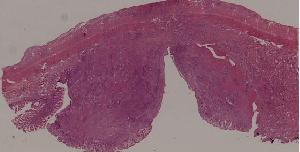

89.淋巴结结核